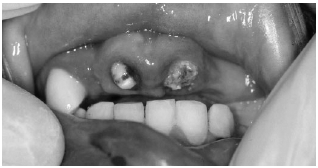

Fractures that extend into the pulp of the tooth are true dental emergencies. (See Figures 1,4) Fractures through the pulp result in pulp necrosis in at least 10-30% of cases even with appropriate initial dental treatment.2 They are distinguished from fractures of the dentin by the pinkish-red color of the pulp. The fracture surface of the tooth should be wiped off with gauze and observed for frank bleeding or a pink blush, which indicates exposure of the pulp. Pulp fractures usually are severely painful, but occasionally there is a lack of sensitivity secondary to a disruption of the neurovascular supply of the tooth.3

| Figure 4. Pulp |